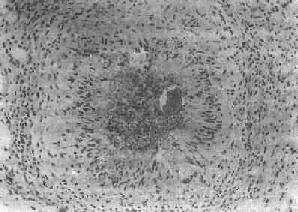

(1)急性虫卵结节:肉眼观为灰黄色、粟粒至绿豆大(0.5~4mm)的小结节。镜下见结节中央常有1~2个成熟虫卵,也偶可多达20个以上。这些成熟虫卵的卵壳上附有放射状嗜酸性的棒状体,也称为Hoeppli现象,用免疫荧光法已证实为抗原抗体复合物。虫卵周围是一片无结构的颗粒状坏死物质及大量嗜酸性粒细胞浸润。因其病变类似脓肿,故也称为嗜酸性脓肿(图19-5)。在坏死组织中可混杂多数菱形或多面形屈光性蛋白质晶体,即Charcot-Leyden结晶,系嗜酸性粒细胞的嗜酸性颗粒互相融合而成。随后虫卵周围产生肉芽组织层,其中有以嗜酸性粒细胞为主的炎症细胞浸润,还有单核巨噬细胞、淋巴细胞、浆细胞及少量中性粒细胞。随着病程的发展,肉芽组织层逐渐向虫卵结节中央生长,并出现围绕结节呈放射状排列的类上皮细胞层。类上皮细胞层逐渐加宽,嗜酸性粒细胞显著减少,构成晚期急性虫卵结节(图19-6),这是向慢性虫卵结节发展的过渡阶段。

图19-6 血吸虫病之晚期急性虫卵结节

坏死区及嗜酸性粒细胞浸润范围缩小,其周围出现放射状排列的类上皮细胞层